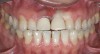

Figure 6  Two-year postoperative image of very conservative Category 1 bonded porcelain restorations.

Figure 6